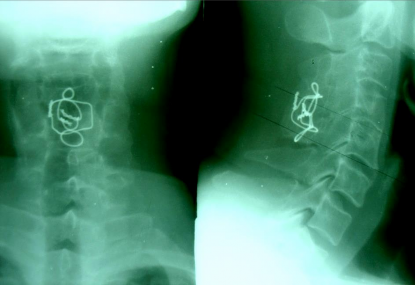

SAU MỔ 9 NĂM (27-5-2011)

CÚI NGỬA

Chỉ KHX vẫn tốt. Liền xương tốt. Cúi –ngửa không di lệch.

(Tầm vận động CSC bình thường)